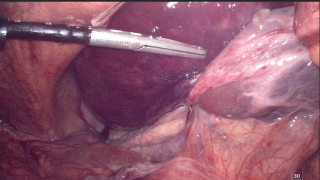

A 77-year-old man with a history of arterial hypertension, chronic alcohol use, gait disorders, and umbilical hernia repair, was admitted with acute left upper quadrant pain and repeated vomiting. Upon admission, vital signs where stable, but clinical exam revealed abdominal distension with peritoneal signs. An abdominal computed tomography scan (Figure 1) showed marked gastric distension, parietal pneumatosis and portal and mesenteric vein gas along with small bowel ileus, without signs of perforation. Additionally, a lesion in the right colonic’s flexure raised suspicion of a neoplasic lesion.

Initial management included nasogastric tube placement via gastroscopy. Exploratory laparoscopy revealed necrosis of the gastric greater curvature (Figure 2), confirmed by intraoperative gastroscopy, which showed transmural necrosis extending to the oesophagogastric junction. The patient’s condition deteriorated, leading to septic shock requiring significant adrenergic support. Following conversion to an open laparotomy, a total gastrectomy was performed, employing a damage control strategy that left the esophageal and duodenal stumps. After achieving hemodynamic stability, the planned second look procedure included eosophagojejunal anastomosis with Roux-en-Y reconstruction, feeding jejunostomy, cholecystectomy, and right hemicolectomy with ileo-colostomy for the suspected neoplasic lesion. Remarkably, the patient recovered without postoperative complications and was discharged to a rehabilitation program.